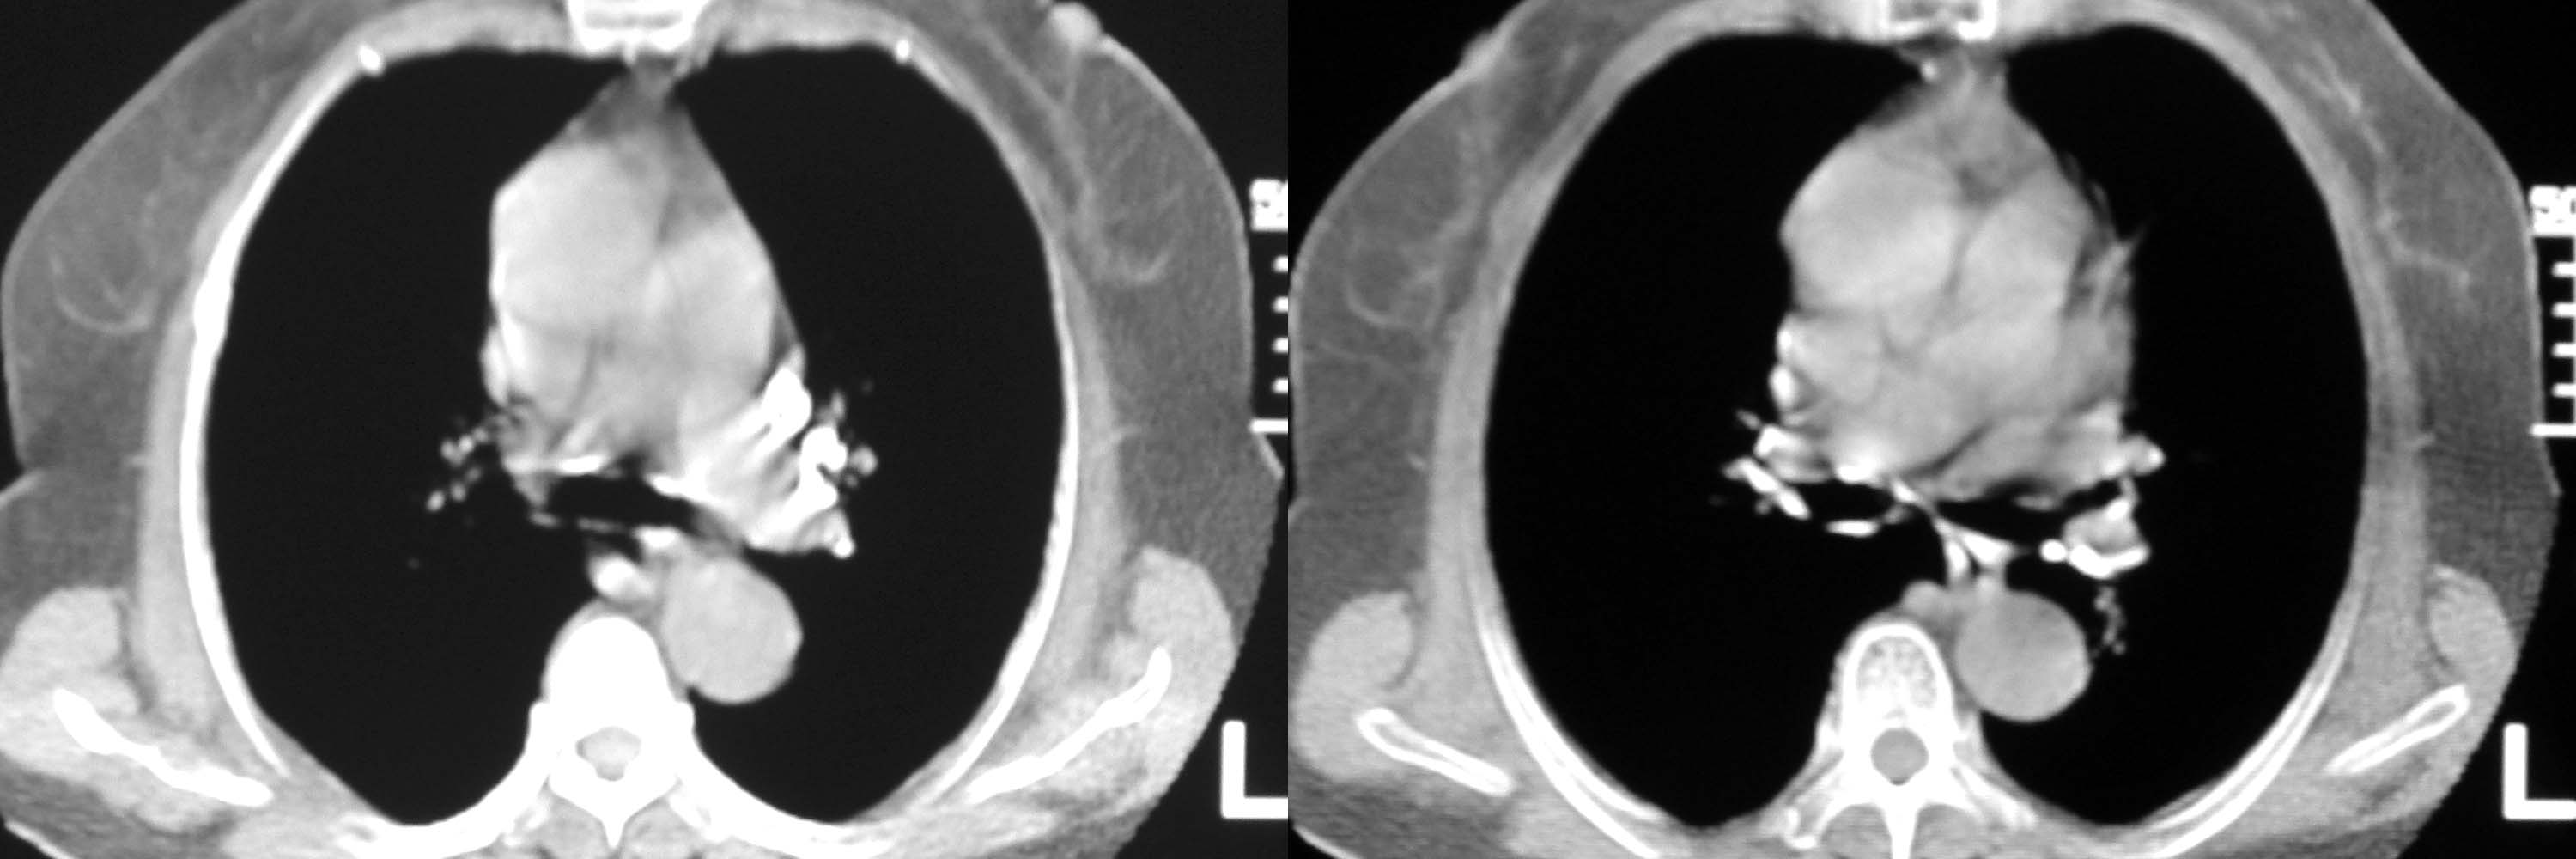

女78岁咳嗽咳痰无咳血平片报右上肺不张、慢支、肺气肿、请老师们帮忙看看,箭头所指是什么?是占位吗?有肺气肿吗?谢谢

箭头所指考虑血管影;纵隔内及双肺门区多发淋巴结钙化;不支持肺气肿。

箭头所指考虑血管影(头臂血管);纵隔内及双肺门区多发淋巴结钙化;不支持肺气肿。